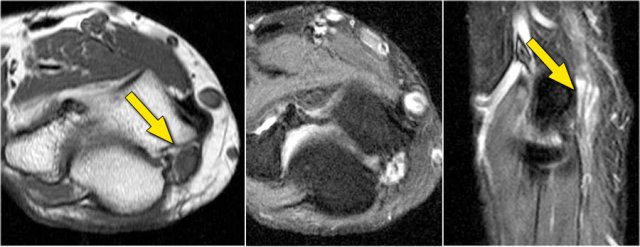

These images are of a 23 year old male who fell onto his outstretched hand two weeks ago while skateboarding.

On physical exam there was decreased range of motion of the elbow and tenderness along the lateral aspect.

What is the structure on the axial image behind the radial head?

• Again the characteristic pattern of marrow edema that is seen in posterior elbow dislocation with contusion in the anterior side of the radial head (red arrow) and on the posterior side of the capitellum.

• The radial head must have hit the posterior part of the capitellum.

The structure behind the radial head is the annular ligament.

It is irregular and thickened as a result of the posterior dislocation.